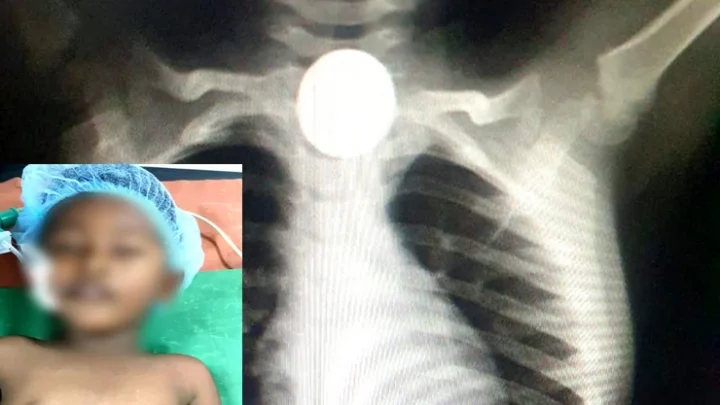

சிறுவனின் தொண்டையில் சிக்கிய ஒரு ரூபாய் நாணயம்… சிகிச்சையில் காப்பாற்றிய அரசு மருத்துவர்கள்!

ஒரு ரூபாய் நாணயத்தை முழுங்கிய இரண்டு வயது சிறுவனை அரசு மருத்துவர்கள் சிறிய அறுவை சிகிச்சை செய்து காப்பாற்றியுள்ளனர்.

திருவண்ணாமலையைச் சேர்ந்த முருகன் என்பவரின் மகன் மீதுன் என்ற இரண்டு வயது சிறுவன் விளையாடிக் கொண்டு இருந்த போது தெரியாமல் ஒரு ரூபாய் நாணயத்தை விழுங்கியுள்ளார். இதையறிந்து அதிர்ச்சியான அவனின் பெற்றோர் தனியார் மருத்துவமனைக்கு அழைத்துச் செல்ல, மருத்துவர்கள் அரசு மருத்துவமனைக்கு செல்ல பரிந்துரைத்துள்ளனர்.

இதையடுத்து அரசு மருத்துவமனைக்கு செல்ல அங்கிருந்த மருத்துவர்கள் எக்ஸ்ரே எடுத்து நாணயம் எந்த இடத்தில் சிக்கியுள்ளது என்பதைக் கண்டறிந்தனர். அதில்  நாணயம் தொண்டையில் இருப்பதை பார்த்தி சிறிய அறுவை சிகிச்சை செய்து நாணயத்தை வெளியே எடுத்து சிறுவனைக் காப்பாற்றினர்.